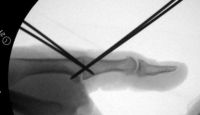

| In this case, 0.045"

K-wires were used for provisional fixation: |

| These were then replaced,

one at a time, with 1.5mm screws. Because of the entry angles, the

countersink bit was used to reduce screw head prominence. |

| Final Result |